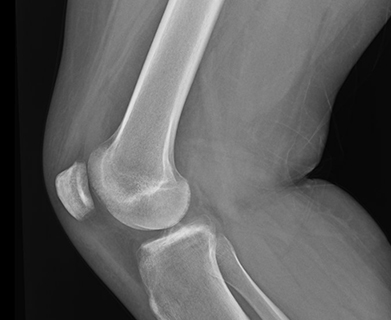

The tibial spine serves as the attachment point for the anterior cruciate ligament (ACL). It is the also the most prominent aspect within the tibial epiphyseal footprint. The tibial spine may not be fully ossified in children and young adolescents which puts them at risk for avulsion fractures of the tibial spine rather than an ACL rupture because of the partial ossification. Figure 1 shows an xray of a tibial spine avulsion fracture in a younger adult, while Figure 2 shows an xray post reduction and surgical fixation.

Figure 2